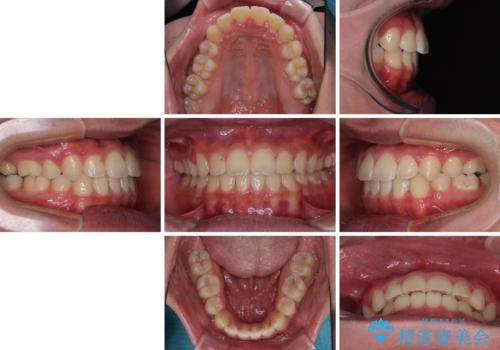

突出した口元 ワイヤー装置で横顔の印象を改善

上顎骨に対して下顎骨がやや前方位に位置しているため、下顎前歯をあまり内側に移動させることができず、口元の突出感改善は期待以上にはならないと予測しておりましたが、満足いくの引っ込み具合となりました。